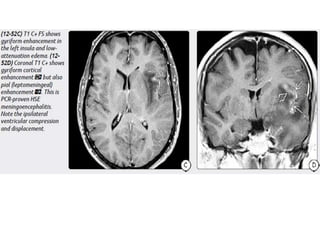

Imaging in CNS Infections